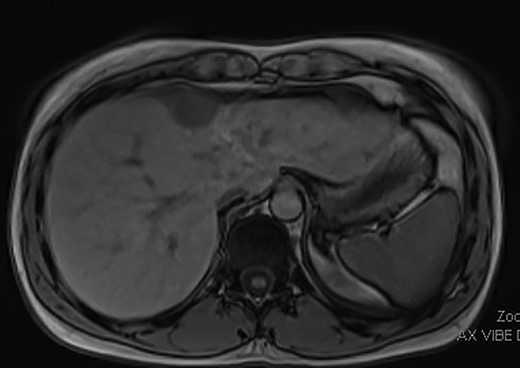

As such, the patient was brought to the operating room for a laparoscopic segment IVa liver resection. Upon insertion of the laparoscope, the mass appeared tethered to the right diaphragm and segment IVa of the liver, and not embedded in the liver parenchyma (Fig. 2). A window was made in the coronary ligament using the harmonic scalpel device. The mass was then dissected circumferentially, taking a bit of the liver capsule with each bite to ensure adequate margins. Once it was freed from the liver side, the dissection was continued at the top of the mass and a few fibers of the diaphragm were taken. A small defect was created in the diaphragm during this dissection, which was closed with metal clips. There were no complications and the patient’s post-operative course was unremarkable other than a small right pneumothorax, which did not require a chest tube. The final pathology from the tumor confirmed metastatic endometrial stromal sarcoma. Multidisciplinary discussion at the British Columbia Cancer Agency recommended active surveillance and no further treatment with megestrol acetate or letrozole necessary.

Metastatic endometrial stromal sarcoma tethered to the right diaphragm and segment IVa of the liver.